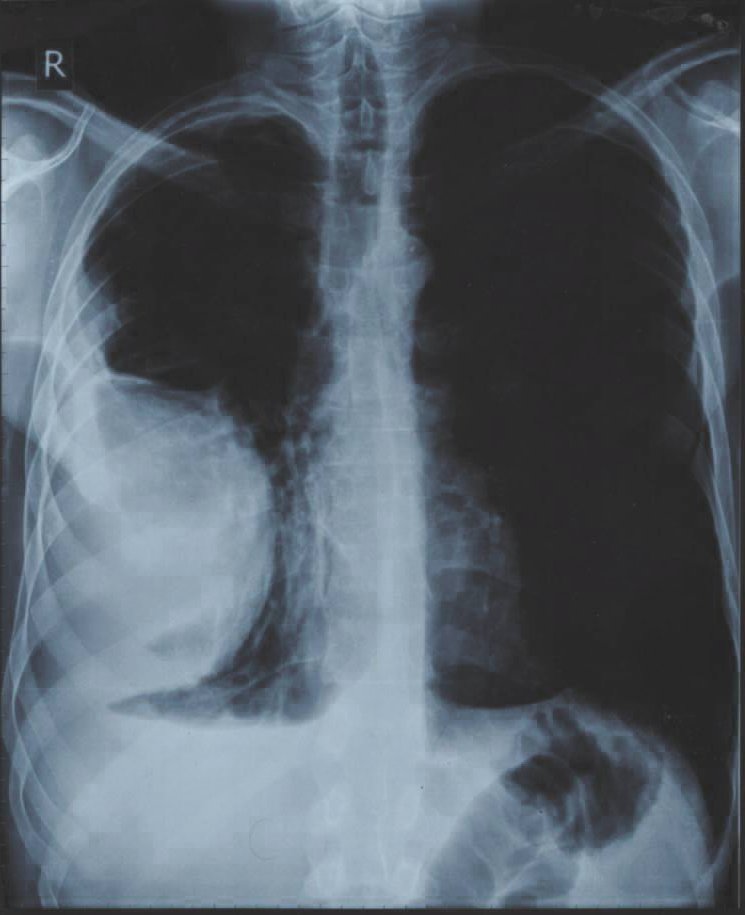

Так или иначе состояние улучшилось настолько, что у меня хватило физических сил наконец-то пройти полное медицинское обследование. Результаты были удручающими, первый же рентгеновский снимок (рис. 1) показал наличие опухоли в лёгком размером с грейпфрут, последующая компьютерная томография показало эту опухоль уже во всей красе (рис. 2). Помимо опухоли, на снимках видно, что заболеванием была полностью затронута печень, именно поэтому организм перестал принимать и перерабатывать пищу. Врачи в один голос требовали срочного оперативного вмешательства. Был поставлен предварительный диагноз – рак, для подтверждения, которого необходимо было провести биопсию, от которой я отказался. Кроме того, мой отказ был мотивирован еще и тем, что вопреки всем исследованиям, по личным ощущениям моё состояние с каждым днем становилось всё лучше.

В феврале 2016 был сделан контрольный снимок (рис. 3). Результат был поразительным, от опухоли не осталось и следа, осталась только соединительная ткань на стенке легкого, на снимке она видна как еле заметная пелена.

И вот ровно через год после первого снимка контрольный снимок показал абсолютно здоровые легкие, без каких бы то ни было следов перенесенной болезни (рис. 4).